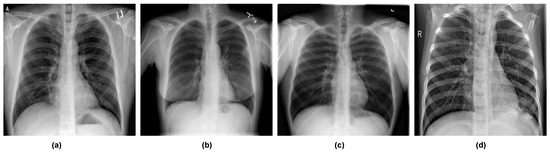

In this study, we used the COVID-19 Radiography Database curated by [93,94], which is publicly available in the Kaggle repository. The dataset comprises 21,165 X-ray images: 3616 COVID-19-positive, 10,192 normal (non-COVID), 6012 lung opacity (non-COVID lung infection), and 1345 viral pneumonia. We experimented with both three and four classes. For four classes, we split the dataset into training (12,696 samples, representing 60% of the entire dataset), validation (6351 samples, representing 30% of the entire dataset), and testing (2118 samples, representing 10% of the entire dataset) sets. For the three classes, we combined lung opacity and viral pneumonia to form one set called viral pneumonia. To increase the number of COVID samples, we performed data augmentation using Augmentor to generate 6000 samples. We then sampled 5000 COVID images, 5000 normal images, and 5000 pneumonia images. We then split the dataset into training (10,499 samples, representing 70% of the dataset), validation (3750 samples, representing 25% of the dataset), and testing (750 samples, representing 5% of the dataset). Table 2 shows the composition of the dataset for four classes and three classes. Figure 5 shows samples of images from the dataset.

Figure 5. Sample datasets used in this work: (a) sample with COVID-19, (b) sample with lung opacity, (c) sample with normal, and (d) sample viral pneumonia.